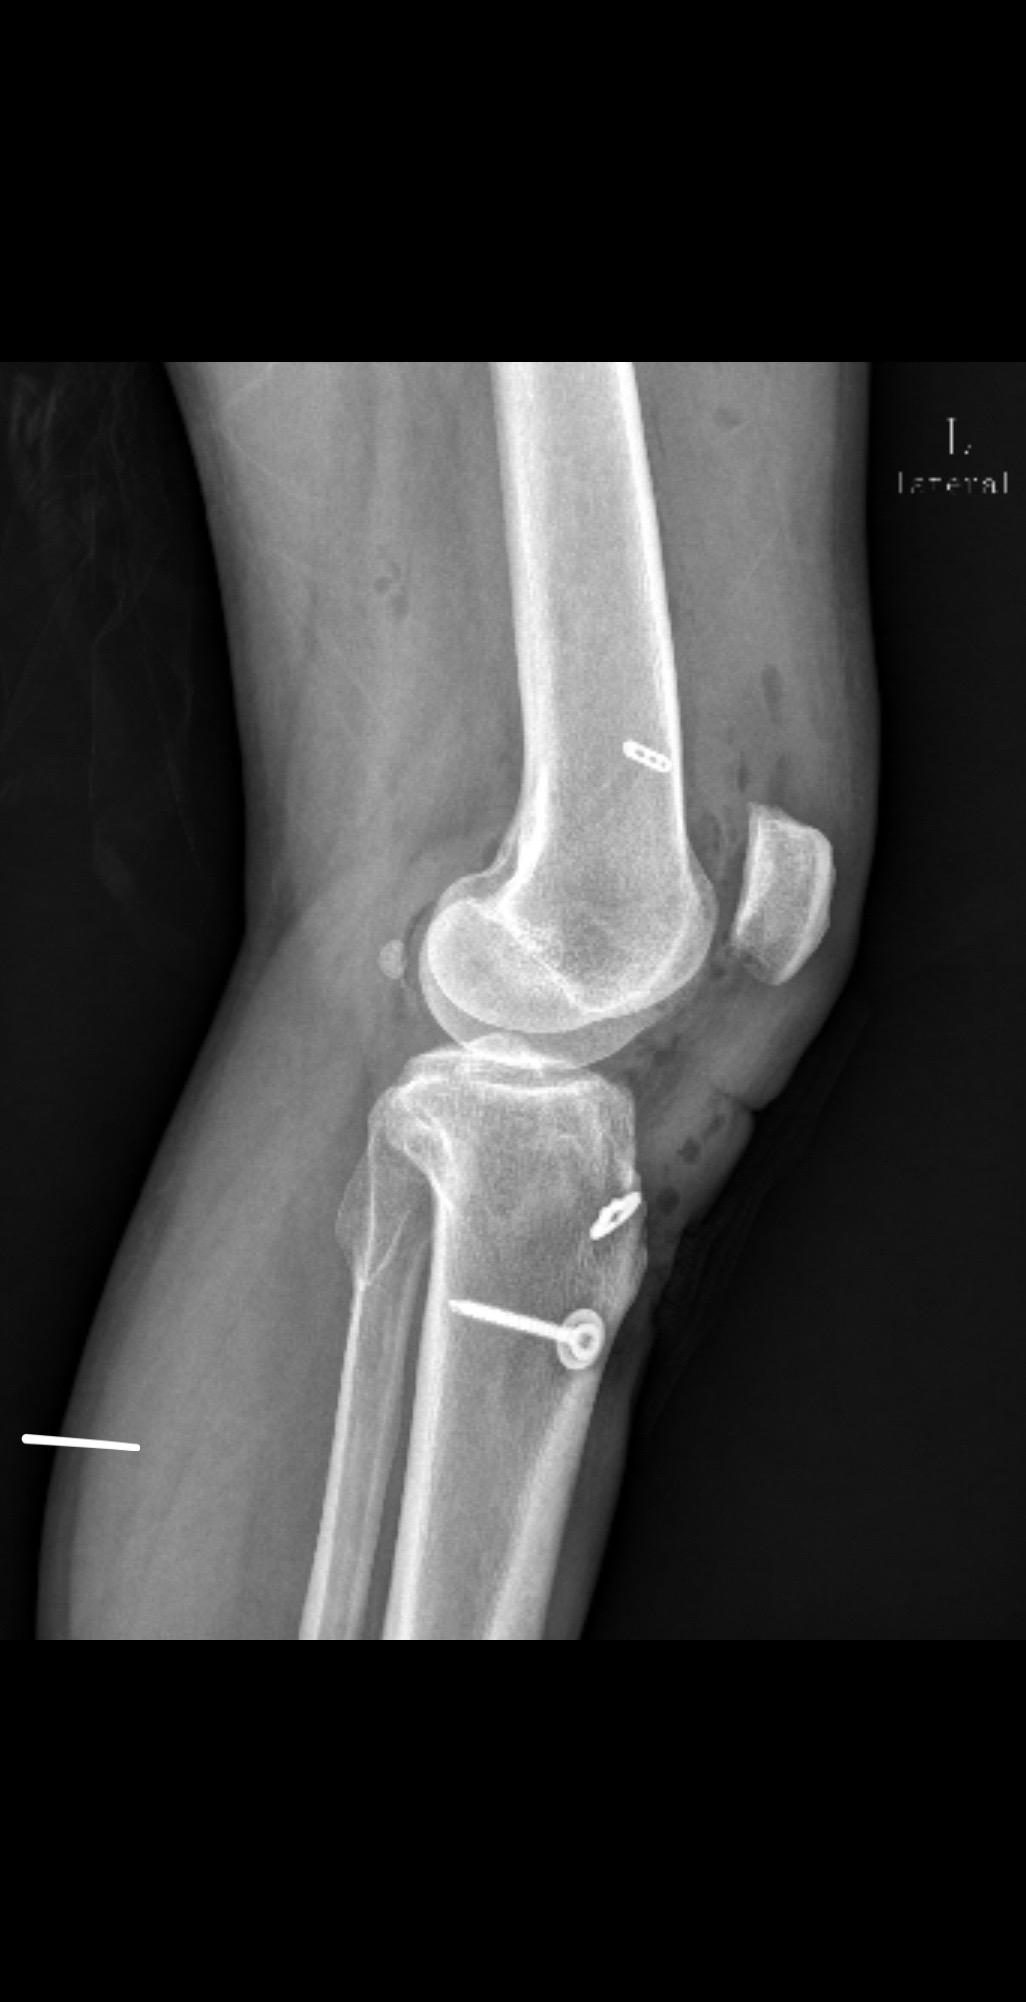

前交叉韧带重建术后影像评估。